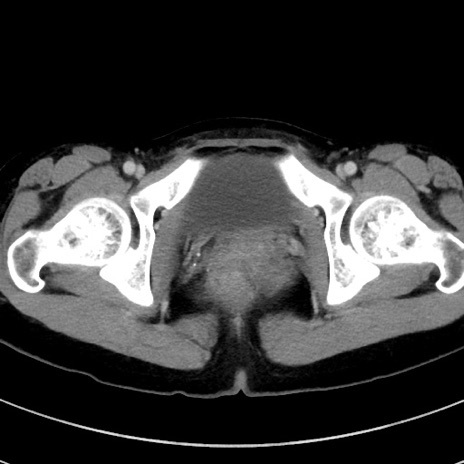

症例17(横断像)

【症例】20歳代女性

【主訴】嘔吐、下腹部痛

【現病歴】昨日夕食後に嘔吐し下腹部痛が出現。本日になっても嘔吐持続し改善しないため来院。

【身体所見】意識清明、BT 37.2℃、BP 108/67mmHg、腹部:平坦、やや硬、下腹部正中から右にかけて圧痛あり、反跳痛軽度あり、tapping pain(+)。

【データ】WBC 13600、CRP 14.94

冠状断像